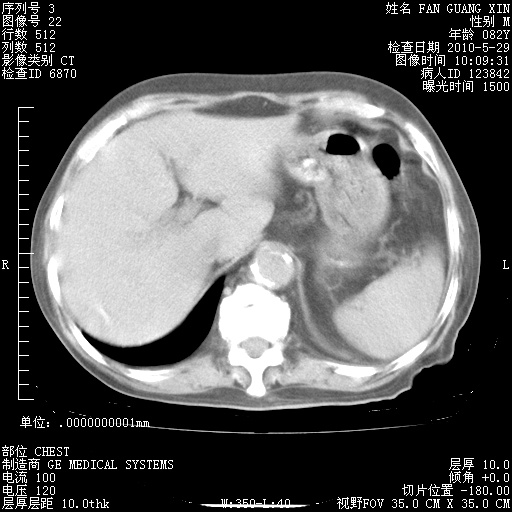

治疗3周后的肺部CT纵隔窗

再治疗10天后的肺部CT